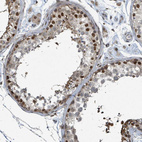

Immunohistochemical staining of human fallopian tube shows strong nuclear positivity in glandular cells.